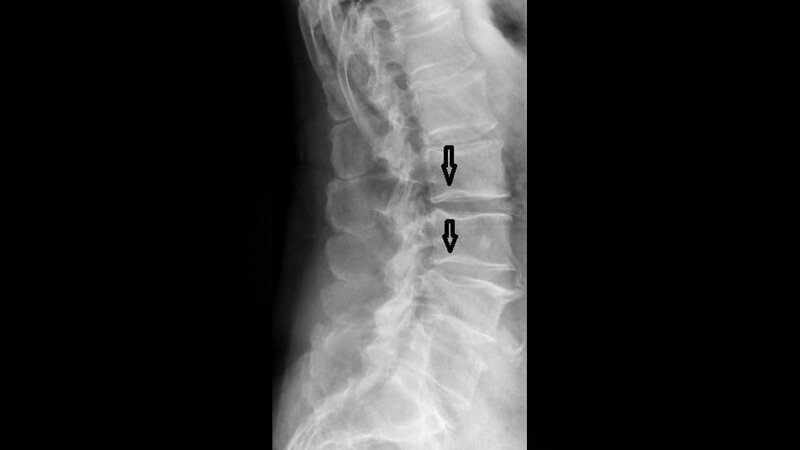

Die Chorda dorsalis ist ein wichtiger Regulator der embryonalen Strukturierung der Wirbeltiere. Eine abnorme Entwicklung der Chorda kann mit etlichen angeborenen Fehlbildungen einhergehen. Die persistierende Chorda dorsalis hat keine Relevanz.

Schlüsselwörter: Persistierende Chorda dorsalis, Röntgen, CT, MRT